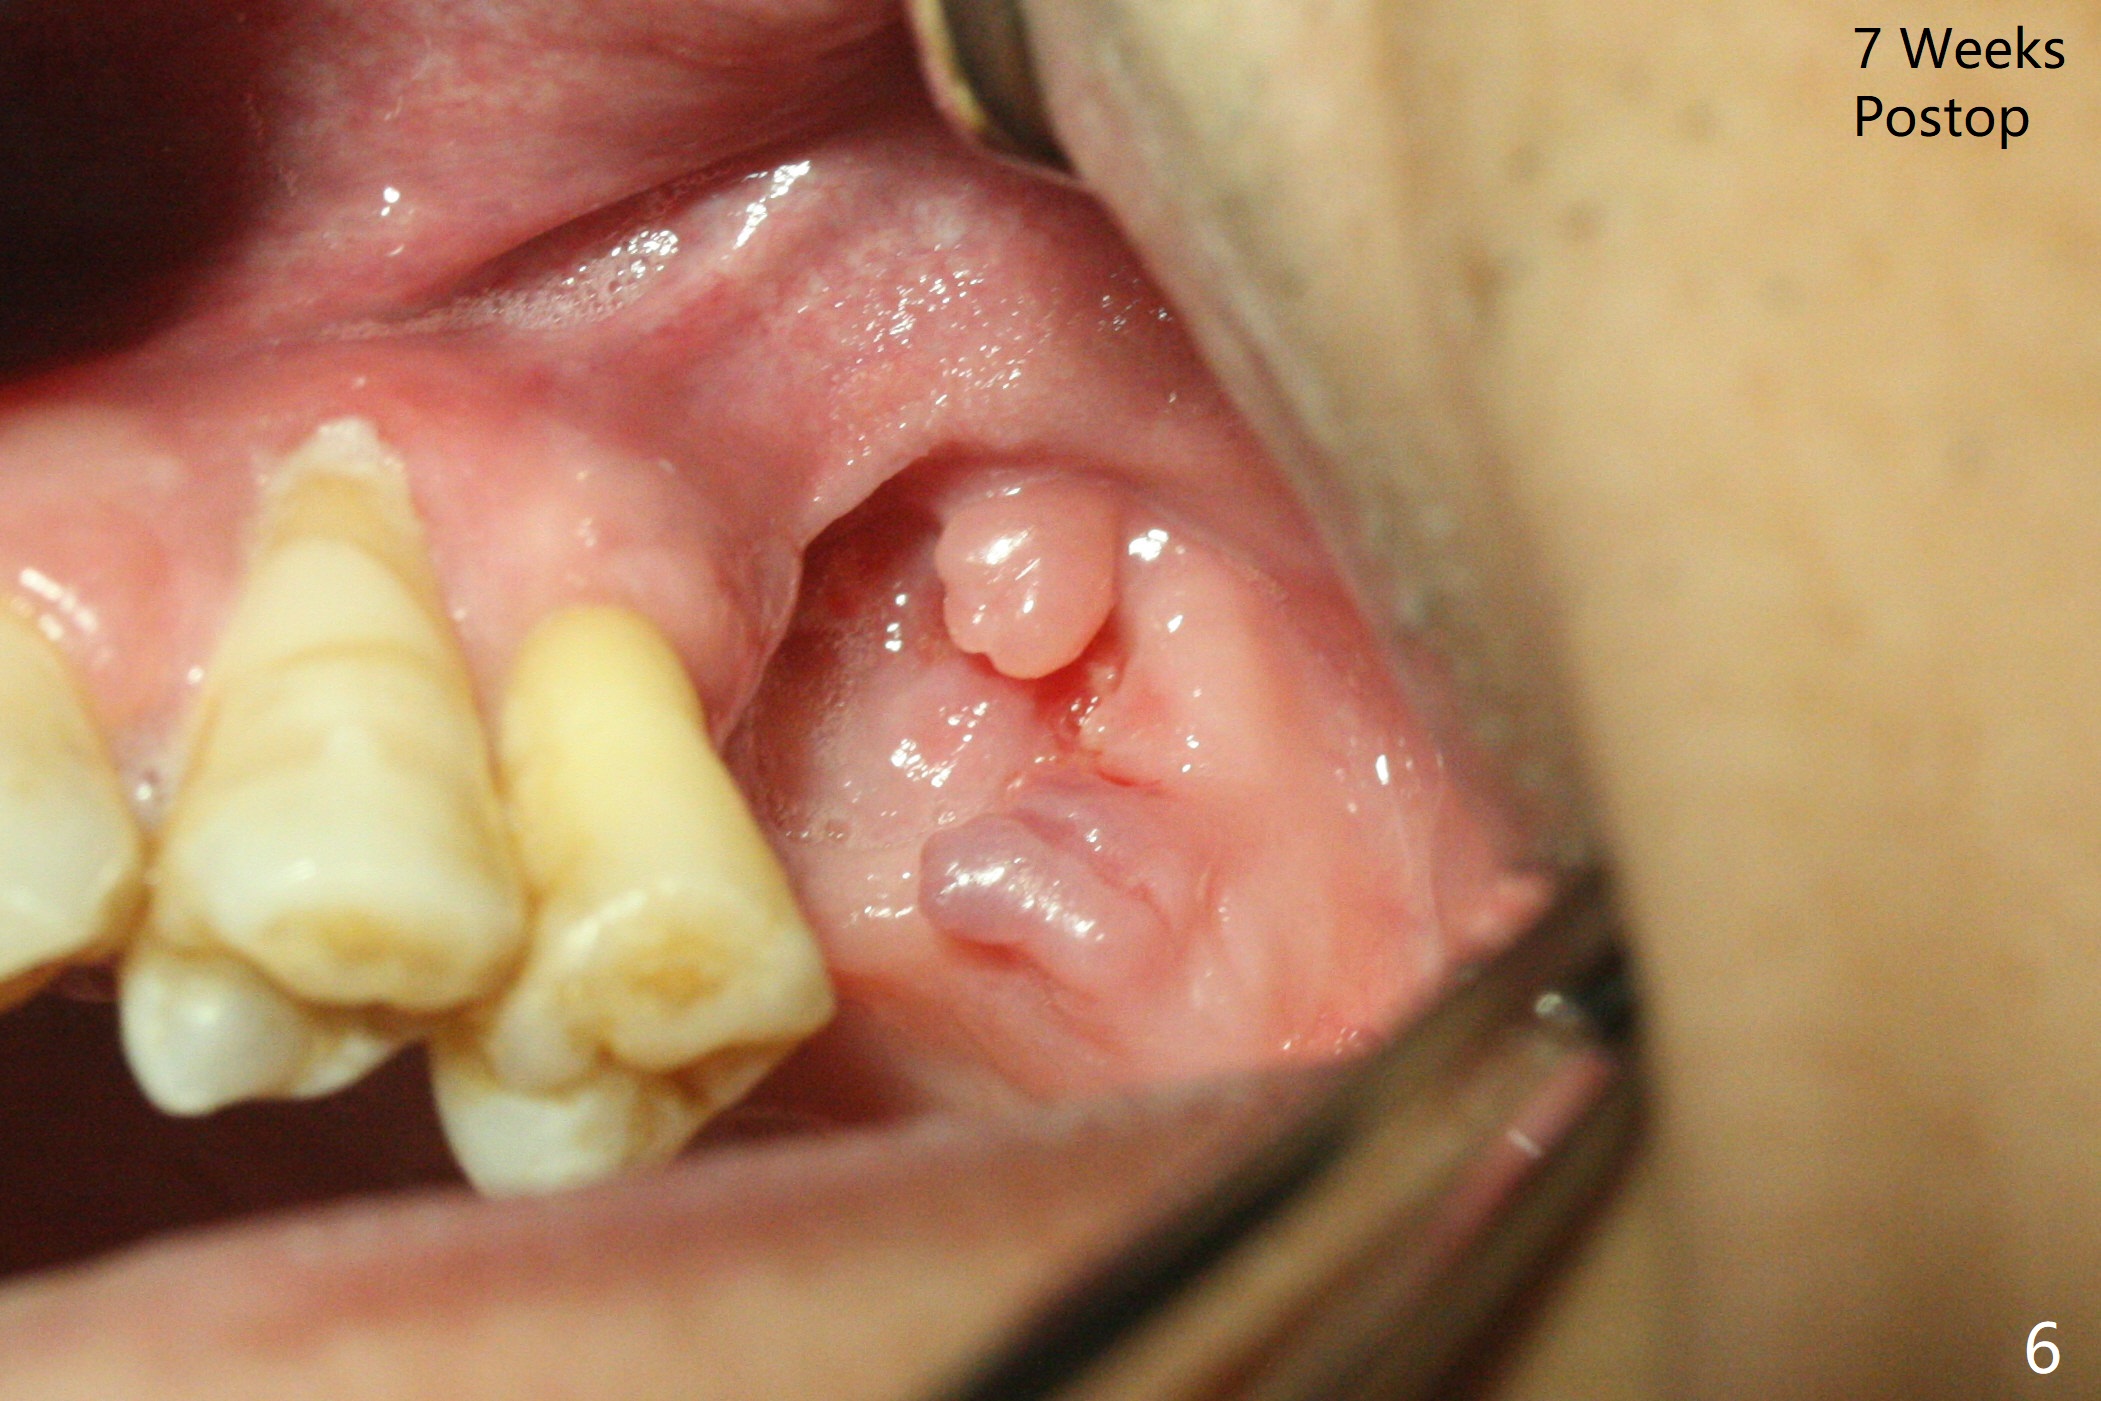

47岁男原本回诊所拔除近中左上智齿(16号牙),影响第一磨牙(14号牙)植牙周围炎治疗后卫生维护。事先制备PRF(图一,二)和骨块(图三 *),拔牙顺利,发现植牙螺纹依然暴露,决定取出植体,上颌窦底板缺失,但膜仿佛完整,放置一小块PRF于上颌窦底,促进上颌窦膜愈合,然后加入新的骨粉,与剩余上清液(图三 >)调袢,虽然不再形成粘性骨块,但是还有好处,放置于拔牙窝以及植牙窝(图四 *),浅部放置骨块(S),这样骨粉不容易丢失,表面再放置PRF膜和不可吸收膜(Cytoplast),使用PTFE缝线。术后7周Cytoplast几乎完全暴露(图五)。当它取出后,骨粉好像损失不少(图六)。二个月后再评价。术后6.5月第一磨牙区仍萎缩(图七),只好再植骨,在第三磨牙区安置一个tenting screw,也在第一磨牙区植入第二个钉子,但是不牢靠,因为仍处于纤维状,把它往上颌窦推作为上颌窦粘膜(图八:>),然后提升(*)。在第一,第三磨牙交界处打入第二个帐篷钉,在两个钉子周围放置粘性骨粉,覆盖PRF膜,缝合。估计植骨效果不佳,植牙时再植骨。